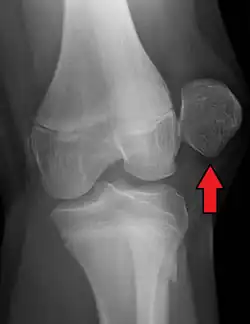

X-ray showing a patellar dislocation, with the patella out to the side.

A patellar dislocation typically occurs when the knee is straight and the lower leg is bent outwards when twisting.[1][2] Occasionally, it occurs when the knee is bent and the patella is struck directly.[1] Commonly associated sports include soccer, gymnastics, and ice hockey.[2] Dislocations nearly always occur away from the midline.[2] Diagnosis is typically based on symptoms and supported by X-rays.[2]